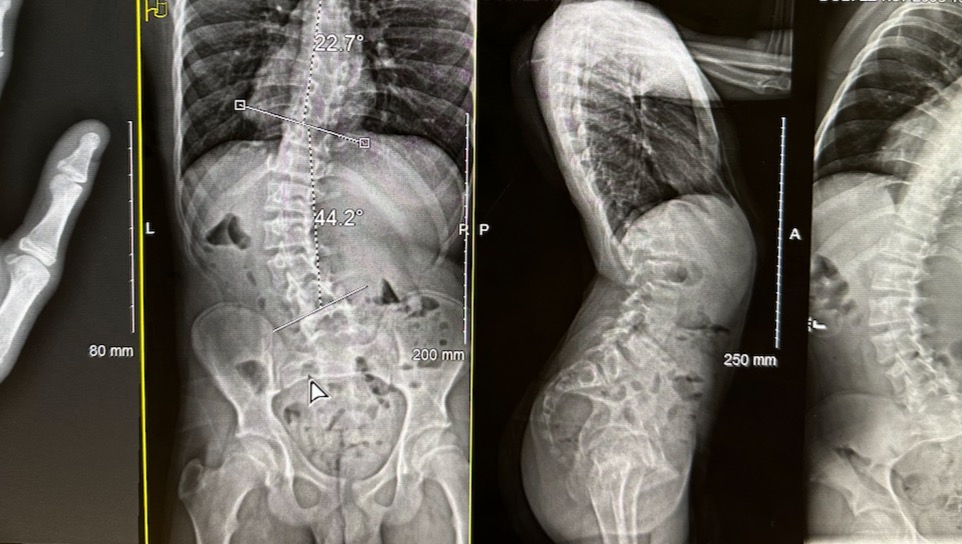

Aidan was diagnosed with scoliosis two years ago. Soon after the diagnosis, doctors at Children’s Wisconsin fit Aidan with a brace. He was compliant wearing it but later had a major growth spurt and went from holding at the 27-degree curvature to an increased curvature of 44-47 degrees, in less than two months. 50 degrees is usually the marker for traditional fusion surgery. Doctors fit him with another outrageously restrictive brace. He is supposed to wear it 18-22 hours a day. I (Denise) liken it to strapping him into the inside of a rolling pin. His movement is severely limited and wearing the brace 20 hours a day has proved impractical and impossible. Worse, Children’s Wisconsin seems to be waiting for Aidan to grow a little more so that they can fuse the majority of his spine. I felt frustrated by the lack of information we were getting and also by what felt like a hopeless march into a surgery that would majorly impact his quality of life.

Aidan’s curvature is in his lumbar-low back. Fusing that part of his spine would make him bend like a Ken doll, severely limiting his movement. Denise researched and found a different kind of spinal surgery that has been pioneered and studied for the last 18 years. It involves a special hardware called a tether. The tether screws are drilled into the vertebrae and hold a flexible cord that helps to push against the curve. As the child grows, the rest of the curve straightens out. The child’s movement is not limited because their spine can still move. It is not a fool-proof method, but it is the greatest chance of preserving movement in the spine. When Children’s Wisconsin told me Aidan would “never” be a candidate for the less invasive VBT, their response struck Denise as not true. She researched more.

I was able to get Aidan a consultation appointment at Shriners Children’s in Philadelphia where they have done over 800 of these surgeries. We met and consulted with their top tethering expert, Amer Samdani, MD, who is their chief of surgery and specializes in both neurological and orthopedic surgery. By networking online, I made early contacts who helped me get Dr. Samdani to look at Aidan’s X-rays. After reviewing the images, he and his staff moved up our appointment. Aidan, Anne, and I flew to Philly on Feb 2.

Meeting the Shriner’s team was incredible. They are brilliant and in less than five hours we visited multiple departments and walked away with more information and answers than we had in two years of appointments in Wisconsin. Dr. Samdani is passionate about preserving movement in the lower spine. He feels Aidan is an ideal candidate for Vertebral Body Tethering (VBT) surgery. As VBT must be done on an immature spine, where the child has growth plates with room to grow, the surgery needs to happen soon. Aidan is nearer to the middle heading toward the end of his growth, thus VBT needs to happen very soon. The surgery is scheduled for May 17 in Philadelphia. We will need to stay in Philly for a week to 10 days.

The surgery is serious. VBT surgeons will collapse his lung and go in from his side to drill into his spinal column and attach the hardware. Dr. Samdani will do the lumbar portion. Another surgeon does the thoracic portion and sometimes there is a third surgeon helping with the procedure. They expect the surgery to last 8 hours and will perform a Double tether on vertebrae T11 to L4 and T12-L3.